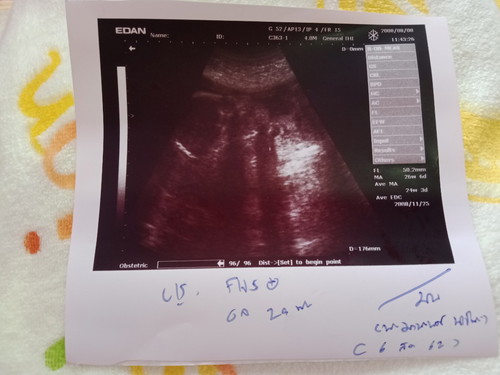

ขอถามแม่ๆหน่อยค่ะดูตรงไหนว่าเปน ญ หรือ ช ค่ะพอดีดูไม่เป็นค่ะ

หญิง หรือ ชาย ค่ะแม่ๆ

กำลังจะเป็นแม่